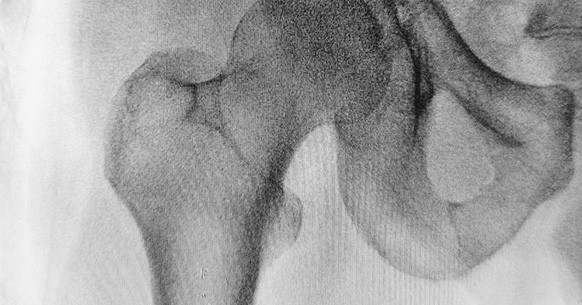

Osteopenia femorale: un problema frequente

L’osteopenia femorale rappresenta una delle forme più diffuse di riduzione della densità ossea, se non la più frequente. Si verifica soprattutto dopo i 50 anni e con prevalenza fra le donne, a causa dei cambiamenti ormonali dovuti alla menopausa. Non a caso, le infiammazioni e le fratture al femore sono molto frequenti nella terza età. Quella al femore appartiene solitamente alle osteopenie di tipo poroso ed è anche uno dei principali campanelli d’allarme per l’osteoporosi.